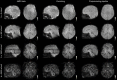

The Developing Human Connectome Project has created a large open science resource which provides researchers with data for investigating typical and atypical brain development across the perinatal period. It has collected 1228 multimodal magnetic resonance imaging (MRI) brain datasets from 1173 fetal and/or neonatal participants, together with collateral demographic, clinical, family, neurocognitive and genomic data from 1173 participants, together with collateral demographic, clinical, family, neurocognitive and genomic data. All subjects were studied in utero and/or soon after birth on a single MRI scanner using specially developed scanning sequences which included novel motion-tolerant imaging methods. Imaging data are complemented by rich demographic, clinical, neurodevelopmental, and genomic information. The project is now releasing a large set of neonatal data; fetal data will be described and released separately. This release includes scans from 783 infants of whom: 583 were healthy infants born at term; as well as preterm infants; and infants at high risk of atypical neurocognitive development. Many infants were imaged more than once to provide longitudinal data, and the total number of datasets being released is 887. We now describe the dHCP image acquisition and processing protocols, summarize the available imaging and collateral data, and provide information on how the data can be accessed.